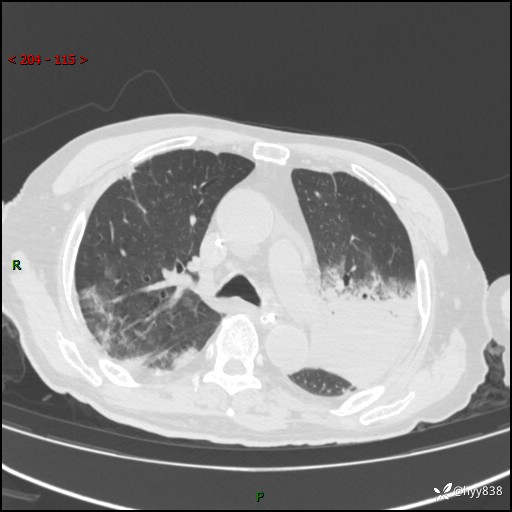

胸部CT复查(2024.8.5)